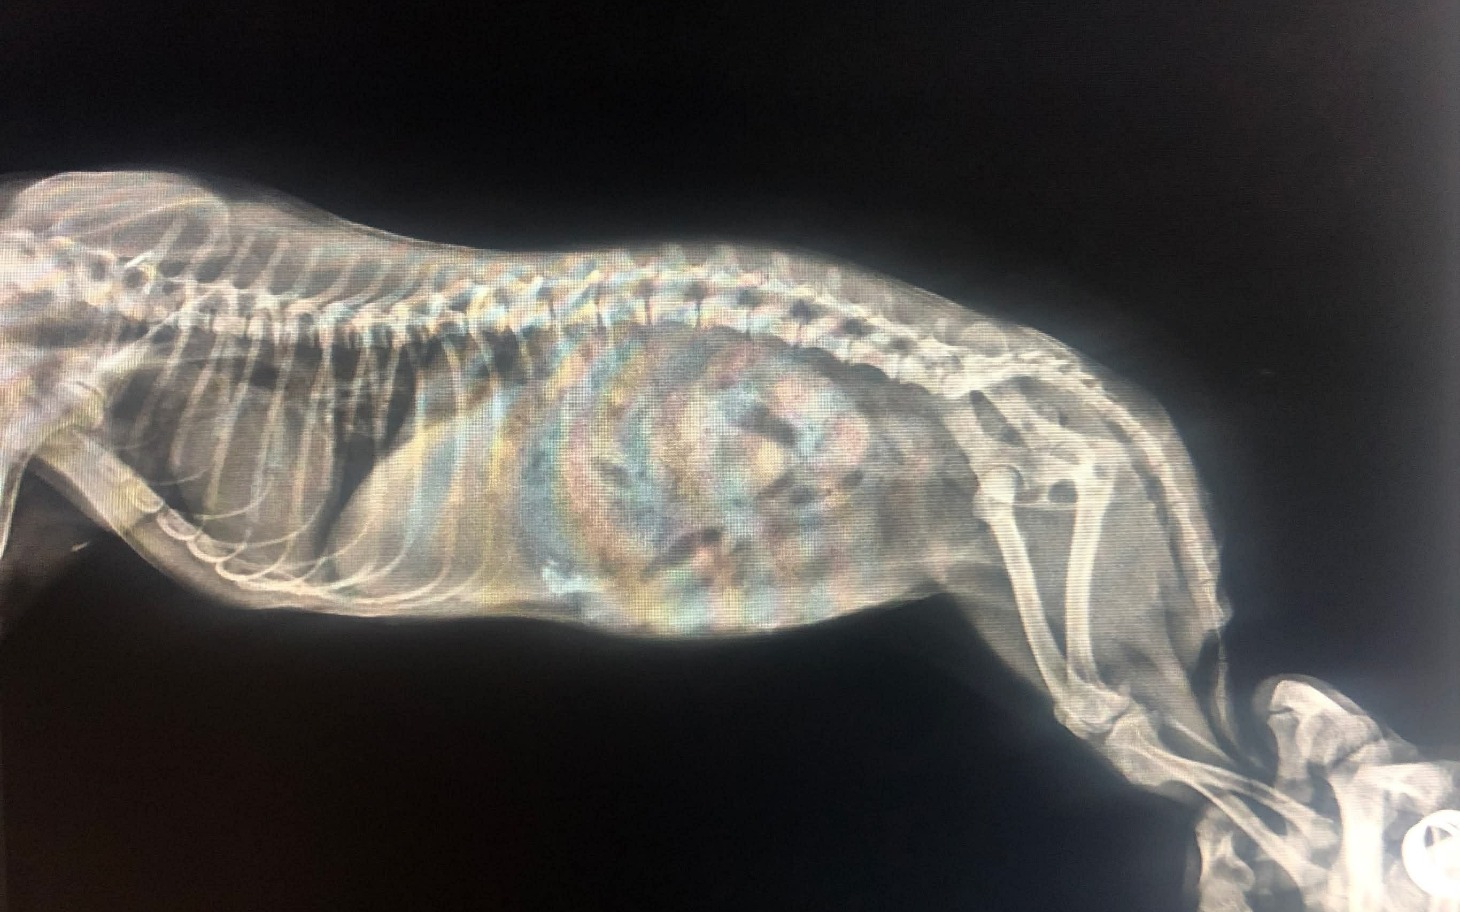

Pomimo ogromu starań, leczenia, konsultacji i dwóch przeprowadzonych RTG, stan jej tylnych łapek wciąż jest zagadką. Co więcej – zauważyliśmy, że dziewczynka nie trzyma kału, co może wskazywać na poważniejsze problemy neurologiczne...

To jedyny sposób, aby sprawdzić, co tak naprawdę dzieje się w jej kręgosłupie i czy istnieje jeszcze jakakolwiek szansa na poprawę jej stanu, komfortu i życia bez bólu.

Z informacji, które otrzymaliśmy wcześniej – sunia najprawdopodobniej została kopnięta przez konia.